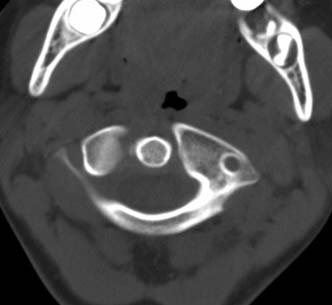

标题: PED0678:男,10岁,寰枢椎平扫。 [打印本页]

标题: PED0678:男,10岁,寰枢椎平扫。

患者在校与同龄孩子打闹后(据家长说被拳击中颈部)出现颈部不适30分钟后入院检查,来时脖子歪斜。请大家看看枢椎齿状突及寰枢关节有问题吗?(3mm层厚断层扫描)。

未见异常

未见明显异常

未见明显异常.再查mri看看。